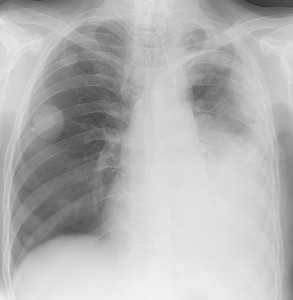

Слева - рак почки с метастазами в легкие, прогноз в данном случае неблагоприятный ввиду метастатического плеврита и дыхательной недостаточности. Определяются очаги с обеих сторон. Справа - мелко- и среднеочаговая диссеминация при раке печени.

Множественные гематогенные вторичные узлы при раке почки, компьютерная томография (КТ).

Гематогенные метастазы саркомы мягких тканей бедра на КТ (справа) и рентгенограмме (слева).

Обратите внимание на увеличение и нарушение структуры корня правого легкого. Это центральный рак. Кроме того, выявлены очаговые тени в обоих легочных полях (гематогенное распространение), а также «лучи», идущие радиально от опухоли корня (лимфогенное распространение).